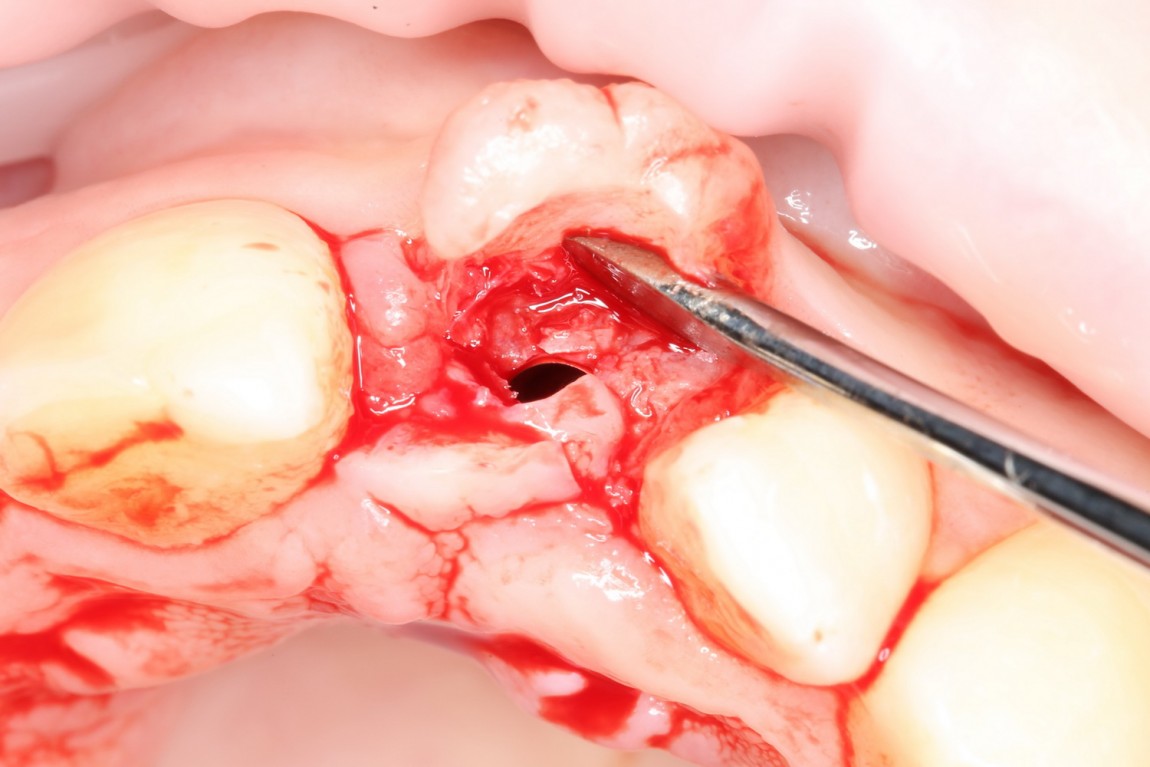

Ответственный момент. Делаем разрез и открываем имплант:

Как видите, вестибулярная стека импланта находится в новообразованной костной ткани. А это значит, что наша остеопластика удалась. Хотя, это еще нельзя назвать результатом нашей операции.

Ставим формирователь десны. Затем, Давид окончательно формирует десну с помощью временной коронки. После его формирования слизистая выглядит примерно так: